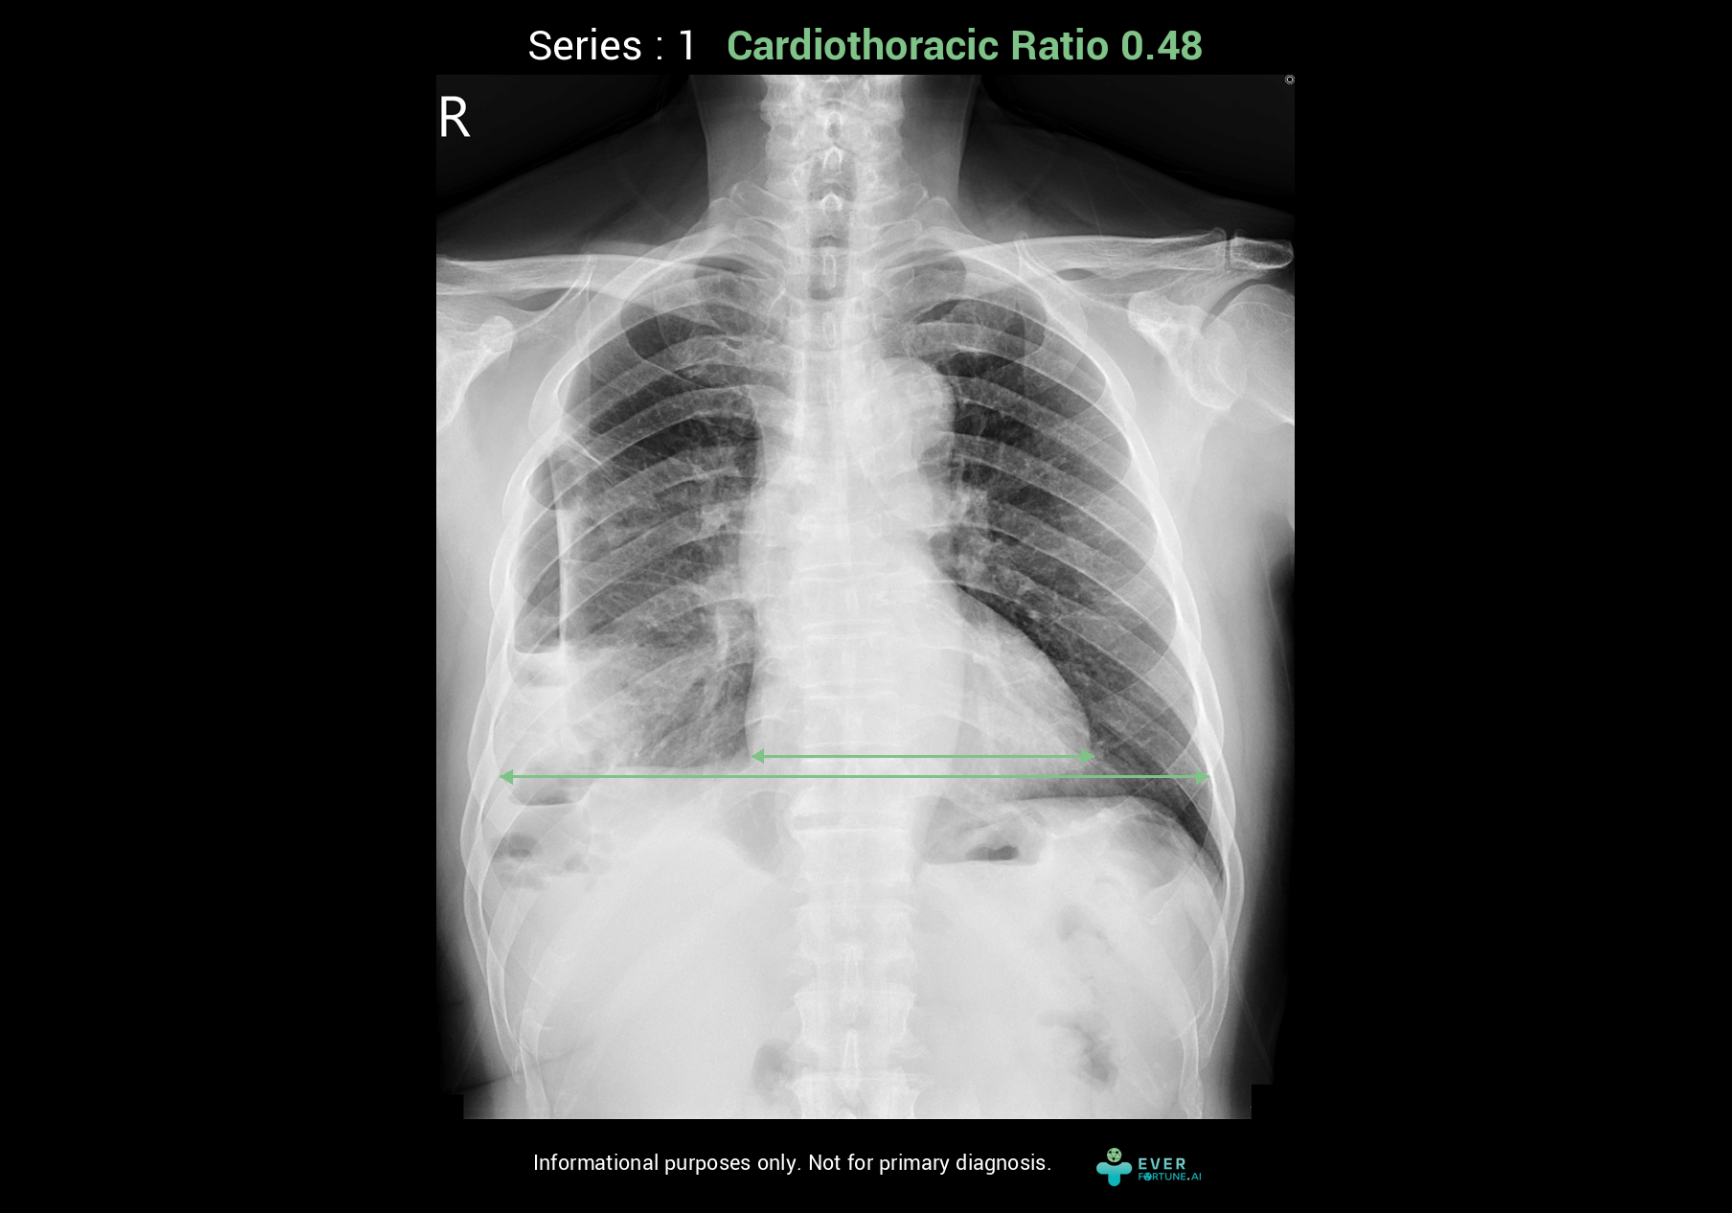

Our AI assistant for chest X-ray interpretation simultaneously assesses pneumothorax, pleural effusion, cardiothoracic ratio, and endotracheal tube depth. It provides key images seamlessly integrated with PACS for fast, highly accurate analysis results.

Identify 15 abnormal finding in chest X-ray images with heart, lungs and bones. The system as a pre-read assistance enable a quick interpretation and faster decisions